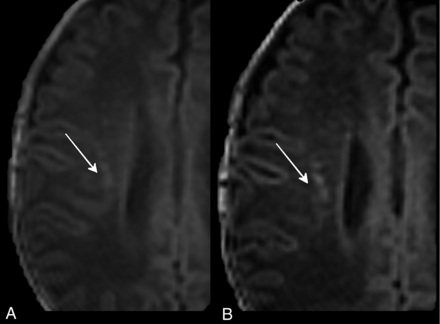

The T1 3D-FFE sequence with a section thickness of 1 mm scored better in identifying HPLs than the other 3-mm T1-weighted sequences (P < .01). In particular, the difference between 1- and 3-mm axial reformatted T1 3D-FFE sequences (P < .01) demonstrated that decreasing the section thickness can significantly increase the detection rate of punctate lesions. This outcome is because the use of thinner sections allowed the separation of contiguous lesions that were seen as confluent with thicker sections (ie, cluster-organized HPLs could be identified as multiple lesions at 1 mm, while they appeared as a single lesion at 3 mm) (Fig 2).

Three-millimeter (A) and 1-mm (B) axial reformatted T1 3D-FFE sequences of PNs affected by PVL. The thinner sections (B) separated lesions that were seen as confluent with the thicker sections (A).